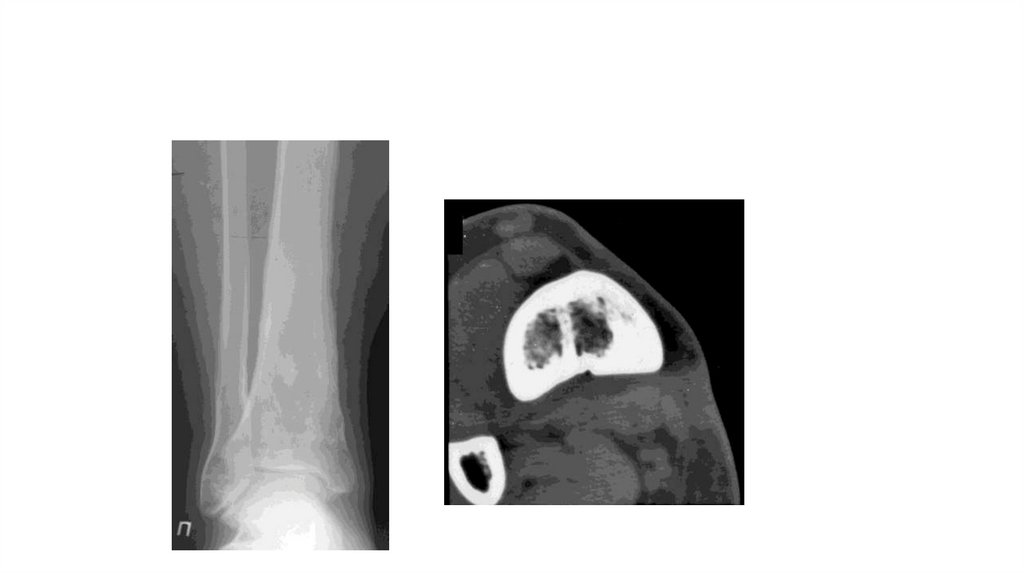

«Воспалительные

заболевания опорнодвигательного аппарата»